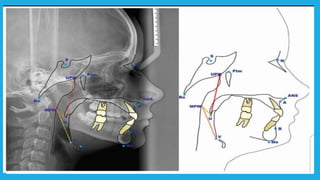

Diagnosis and treatment planning

Diagnosis and treatment planning for combined

orthodontic and orthognathic surgical patient

should follow the same sequence that used for

orthodontic treatment planning by taking

 Radiographic assessment of the patient